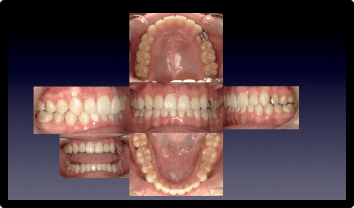

叢生を矯正治療で改善した症例

BEFORE

AFTER

症例概要

年代・性別

30代 男性

主訴

歯並びがたつき気になる。噛み合わせよくしたい。

治療内容

インビザラインライト

治療期間

1年8ヶ月

治療のリスク

歯が染みたり、後戻りする可能性があります

治療費用

935,000円(税込